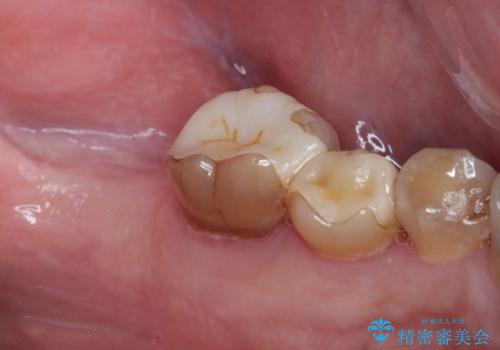

- 左下奥歯のインプラント治療と左上の被せもののやり替えを希望されて来院された患者様です。

左上の奥2本は他院で根管治療と仮歯まで入れている状態です。根管治療のやり替えは希望されなかったため被せものから治療していくことにしました。